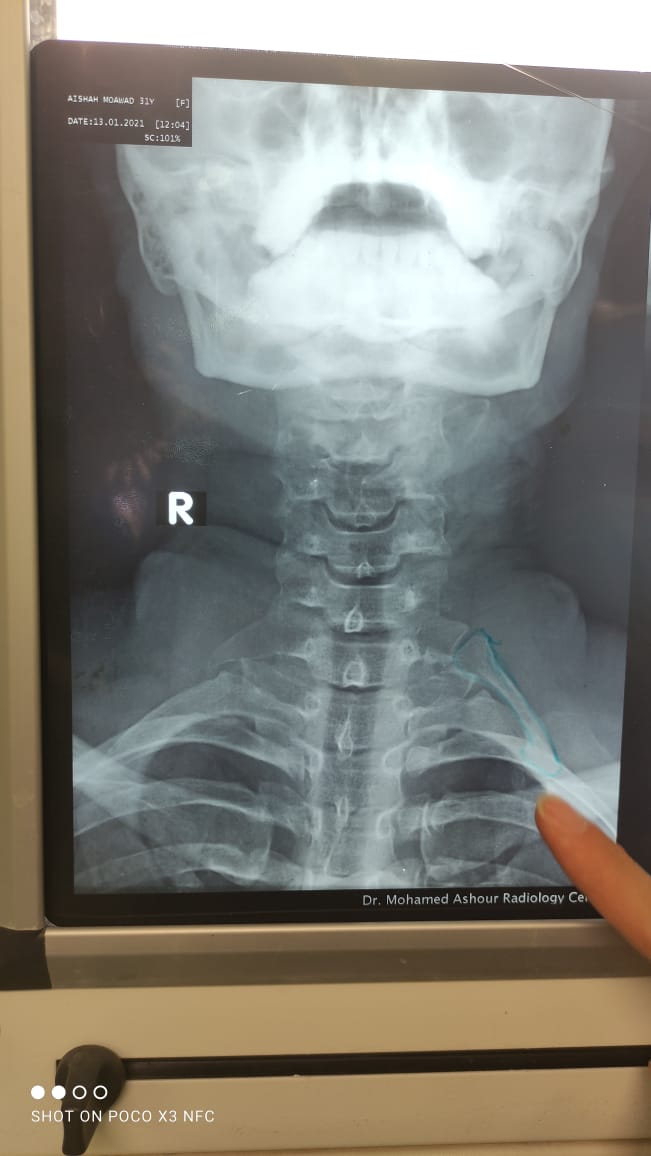

مستشفى جامعة أسوان تستئصل ضلعا زائدا برقبة مريض

صرح الدكتور محمد زكي الدهشوري عميد كلية الطب رئيس مجلس إدارة المستشفيات الجامعية بأسوان أنه تم نجاح فريق طبي بقسم جراحة الأوعية الدموية بمستشفيات جامعة أسوان في اجراء عملية جراحية كبري

باستئصال ضلع زائد بالرقبة (الفقرات العنقية) لمريضة تعاني من تورم بالذراع الأيسر مع حدوث جلطات متكررة بالاوردة العميقة بالذراع الايسر وقد تم استئصال الضلع الزائد كامل.